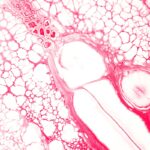

Questa patologia rara e complessa, caratterizzata da un accumulo depositi di proteine anomale, chiamate amiloidi, nei tessuti e negli organi di tutto il corpo, colpisce un numero limitato di pazienti nella nostra regione e richiede un approccio altamente specializzato. Senza una terapia che blocchi l’accumulo di amiloide, il danno degli organi colpiti è progressivo fino ad arrivare a una compromissione molto grave.

In Italia si stimano circa 800 nuovi casi ogni anno. La “AL” è una tra le più comuni amiloidosi, di cui si conoscono circa trenta tipi diversi, ciascuno causato da una diversa proteina. Ogni tipo richiede una terapia differente e personalizzata e controlli frequenti per monitorare l’efficacia della cura e il danno dell’organo.